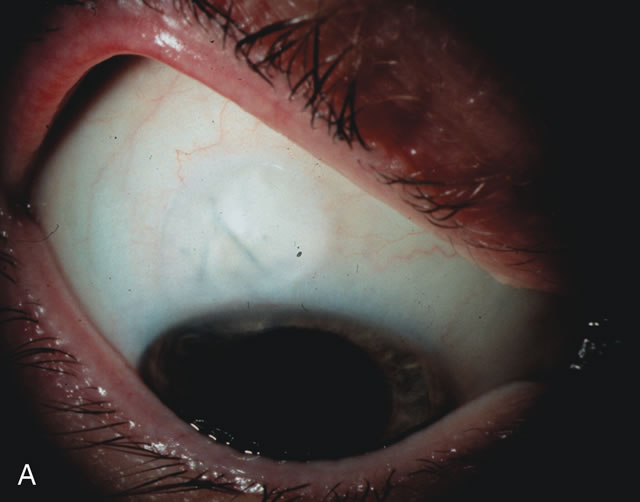

During preoperative slit-lamp biomicroscopy, the surgeon evaluates the condition of the conjunctiva and decides on a fornix-based or a limbus-based conjunctival approach.174–177 There are definite advantages and disadvantages of each approach (Table 3). With proper wound construction, there appears to be very little difference in long-term IOP control between the two incisional groups. However, the long-term bleb appearance varies considerably between the two incisional groups,178 with a limbus-based conjunctival flap more likely to develop a cystic bleb especially if an antimetabolite is used179 (Fig. 8).

Fig. 8. Bleb appearance after limbus-based versus fornix-based conjunctival flaps. Even though the IOP is thought to be equivalent between limbus and fornix-based conjunctival flaps, the final bleb appearance varies considerably. A. During a limbus-based approach, an incision through conjunctiva 10 mm posterior to limbus will sever through multiple arterial vessels, increasing the likelihood of an avascular bleb. B. The tissues are dissected down to the sclera further cutting feeder vessels from Tenon's capsule. C. The wound is closed inciting a cascade of wound healing events that may ultimately lead to scarring producing a barrier to aqueous flow. D. This leads to walling off of a bleb that has lost some of its overlying vascularity (pale cystic avascular bleb). E. During a fornix-based conjunctival approach, the incision is made at the limbus and tissues undermined. F. The incision is closed at the limbus; no conjunctival vessels are severed over the bleb area. G. This fosters the formation of a shallow diffuse pale bleb with a normal vessel pattern.